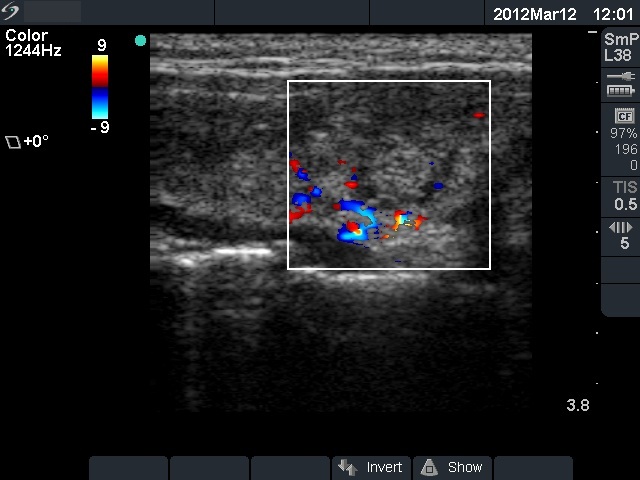

11 months after init. investig. |

7.30 |

0.18 |

4 months after delivery |

Nothing |

71 |

0.24 |

11.9 |

The ultrasound pattern of de Quervain's thyroiditis and that of papillary cancer are very similar: a hypoechogenic lesion with blurred borders are found in both cases. They differ in vascularization statistically but the vascular pattern has only limited practical significance. In the acute phase of de Quervain's thyroiditis the vascularization is generally decreased but even in this case the situation was the opposite. The finding of not one but multiple hypoechogenic areas favored the possibility of subacute thyroiditis.

The relapse of de Quervain's thyroiditis in the contralateral lobe is a very frequent finding but not one year after the appearance of the disease. We supposed that the immunological changes during and after pregnancy explained the relatively late relapse of the disease.